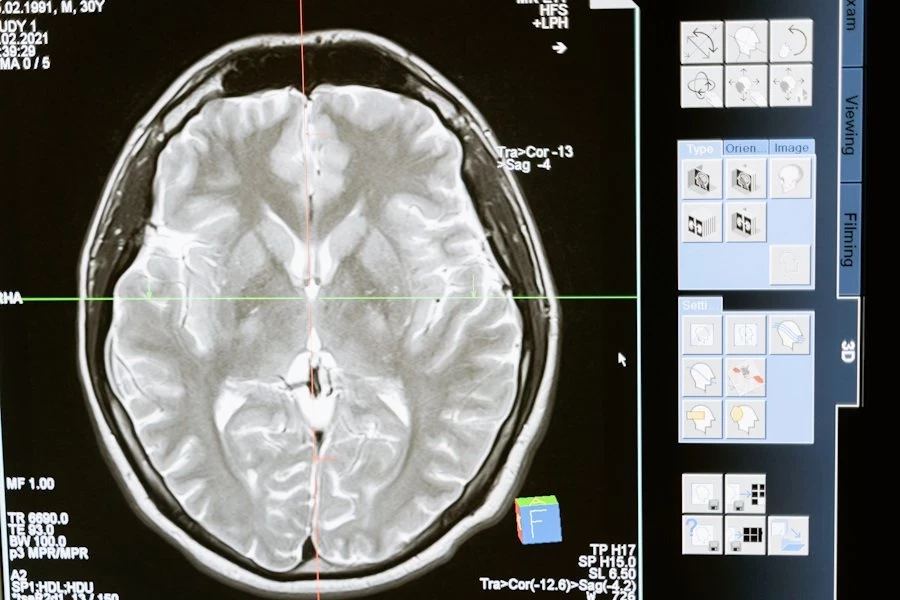

NEJM: комбинация препаратов уменьшила опухоли головного мозга на 91%

В Harvard Medical School ученые разработали новое лечение для редких опухолей головного мозга, называемых папиллярными краниофарингиомами. Их методика выдала потрясающие результаты в уменьшении размеров опухоли. Они опубликовали свою методику в журнале New England Journal of Medicine.